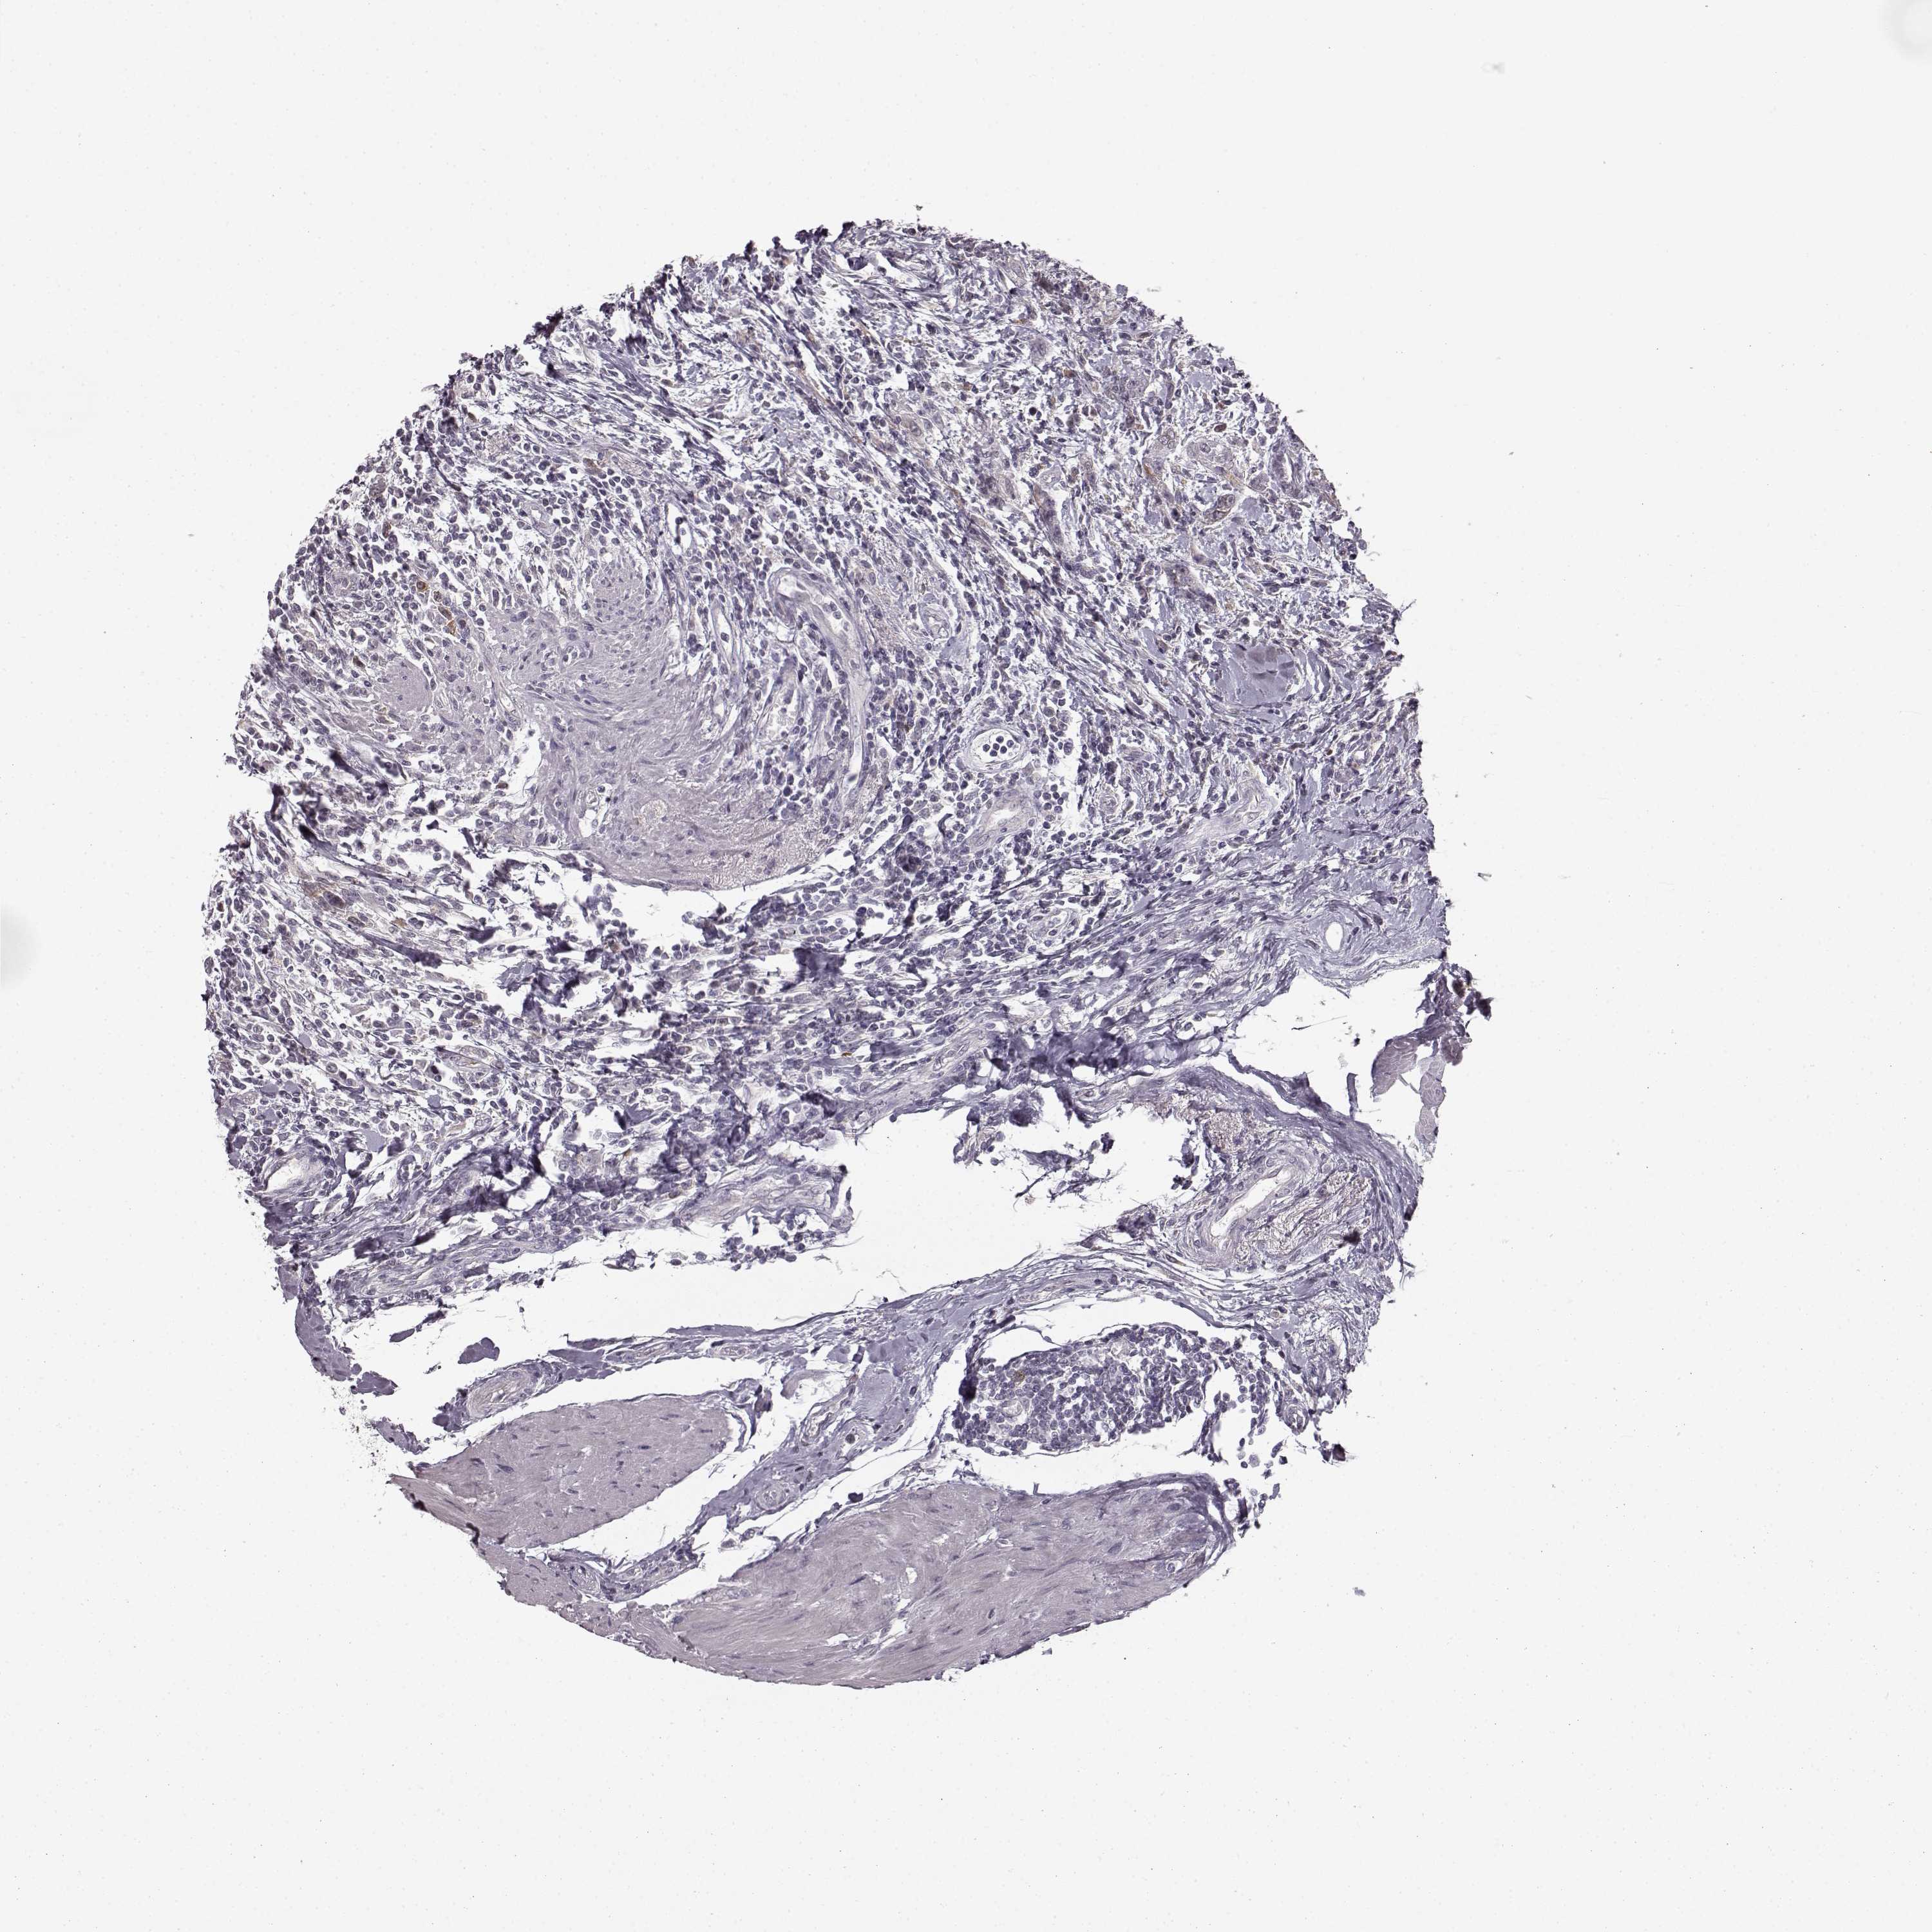

UROTHELIAL CANCER - Protein expressioni

A mouse-over function shows sample information and annotation data. Click on an image to view it in a full screen mode. Samples can be filtered based on level of antibody staining by selecting one or several of the following categories: high, medium, low and not detected. The assay and annotation is described here.

Note that samples used for immunohistochemistry by the Human Protein Atlas do not correspond to samples in the TCGA dataset.

Antibody stainingi

Antibody staining in the annotated cell types in the current human tissue is reported as not detected, low, medium, or high, based on conventional immunohistochemistry profiling in selected tissues. This score is based on the combination of the staining intensity and fraction of stained cells.

Each image is clickable and will lead to virtual microscopy that enables deeper exploration of all samples and also displays staining intensity scores, fraction scores and subcellular localization as well as patient and tissue information for each sample.

Antibody HPA040025

Antibody CAB002433

Urothelial carcinoma, High grade

Urothelial carcinoma, NOS

Urothelial carcinoma, Low grade